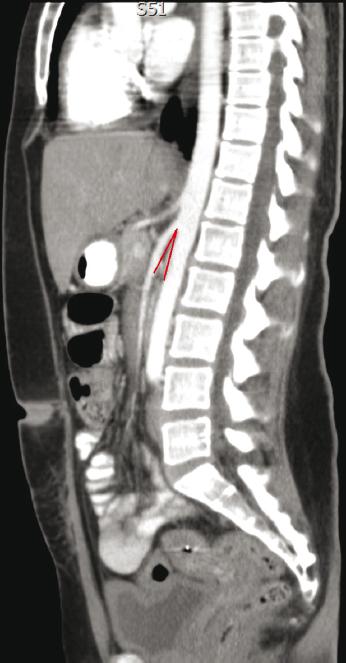

The patient is a 36-year-old female with a medical history of diabetes mellitus type 2 of a recent diagnosis. She began complaining of nausea, bilious vomiting, and a recent weight loss of 12 kg in the past 3 months. An esophagogastroduodenoscopy showed a dilated stomach but no evidence of gastric outlet obstruction. However, the study demonstrated an extrinsic partial obstruction of the third part of the duodenum (Fig. 1), with important dilation proximally. Thereafter, the patient underwent contrast-enhanced computed tomography (CT) scan of the abdomen and pelvis that revealed a dilated stomach and duodenum up to the level of the third part, and a sudden narrowing just anterior to the abdominal aorta and posterior to the SMA; also, a significant reduction of the aortomesenteric angle and distance was seen (Fig. 2), being of 13° and 6 mm, respectively. With these clinical and radiologic findings, the diagnosis of SMA syndrome was made. The patient was admitted and started on IV hydration and gastric decompression through a nasogastric tube and total parenteral nutrition. The patient did not improve with conservative treatment so a surgical procedure was planned.

Figure 2 Double contrast-enhanced computed tomography scan where an aortomesenteric angle of 13° is observed.

Anatomically, the normal range of aortomesenteric angle varies between 25° and 60° and aortomesenteric distance ranges between 10 mm and 28 mm, in this case, the measurements were 13° and 6 mm, respectively. The third part of the duodenum lies just posteroinferior in relation to SMA. Any loss in retroperitoneal fat might reduce that angle and leads to Wilkie’s syndrome7,8.